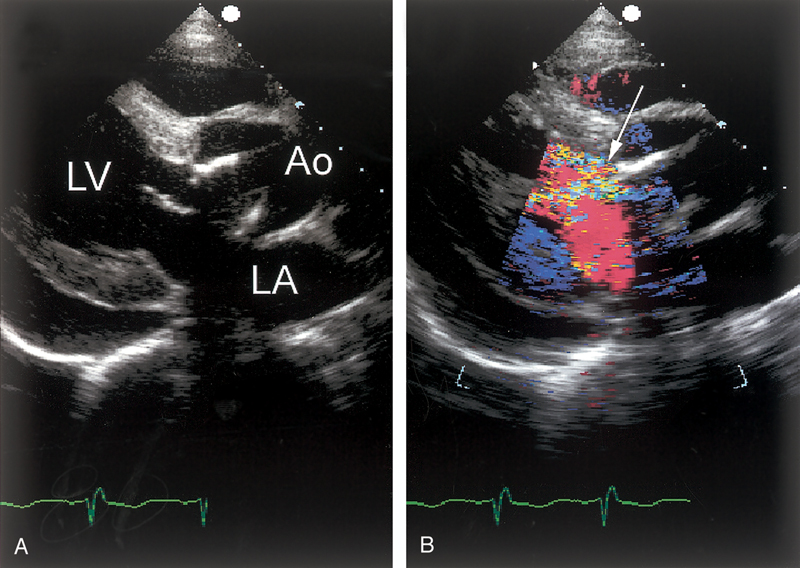

فحوصات تشخيصية لبعض امراض القلب والشرايين التاجية